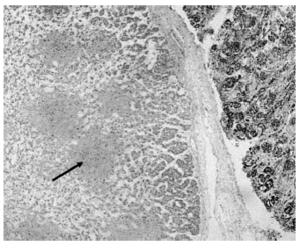

El informe anatomopatológico del feto objetivó la presencia de microabscesos viscerales por infección por Listeria (fig.1). En la placenta se apreciaron también microabscesos inter-intravellositarios (fig. 2).

Figura 2. Microabscesos intra e intervellositarios de placenta. Hematoxilina-eosina. 20X.